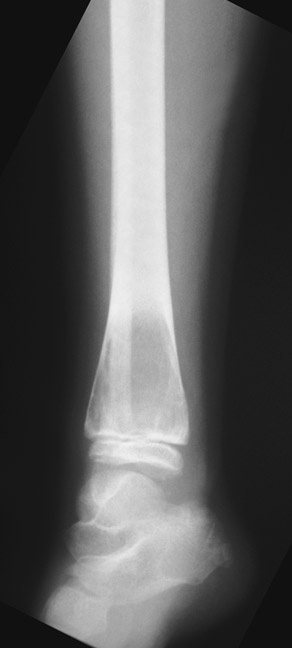

Aneurysmal Bone Cyst